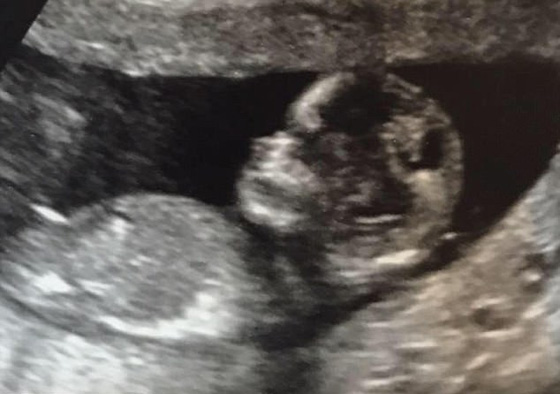

تنتظر أكبر أسرة بريطانية مولودًا جديدًا، ليصبح عدد الأبناء فيها 20 ابنا وابنة، مؤكدين انه سيكون الابن الأخير. وجميعهم يتشاركون 10 غرف في المنزل، وحماما واحدا فقط، مما يجعل عملية الاستحمام صعبة وبحاجة الى تنسيق مسبق بين الجميع و"حجز" أدوار. والروتين اليومي في المنزل يبدو أعقد وأطول وقتًا، فوقت الاستحمام يبدأ لديهم من الساعة السادسة مساءً، حيث تقوم الأم بمساعدة الأطفال الصغار، بينما يظل الأبناء الأكبر حتى الساعة التاسعة مساءً، كي يستحموا.

تنتظر أكبر أسرة بريطانية مولودًا جديدًا ليصبح عدد الأبناء فيها 20 ابنا وابنة